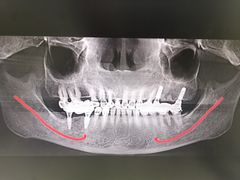

• 牙博士口腔品牌连锁(杨浦店)

• -牙博士口腔品牌连锁(杨浦店)